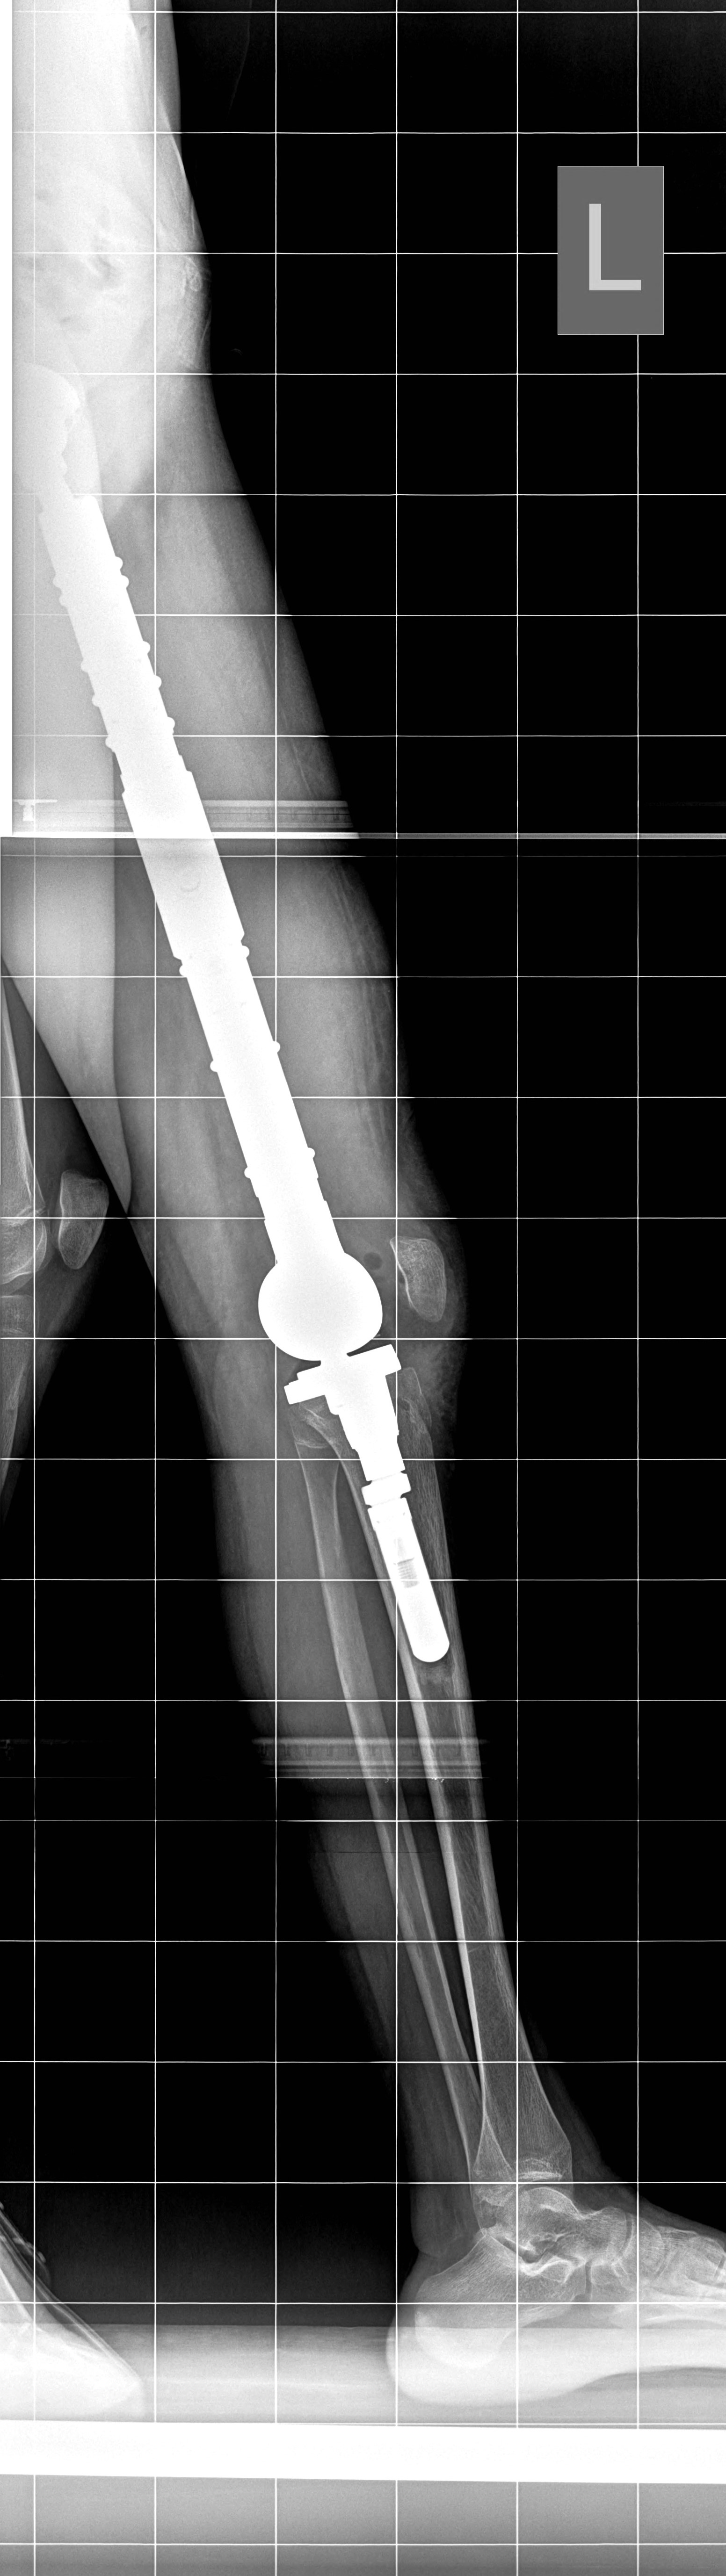

Две седмици след уникална операция в Университетската специализирана болница за активно лечение по ортопедия “Проф. Бойчо Бойчев” в Горна баня 13-годишната Райна Т. от Пловдивско може отново да ходи с двата си крака. Момичето постъпва в ортопедичната болница със страховитата диагноза Сарком на Юинг, обхващащ лявото бедро по цялото протежение. След проведена предоперативна химиотерапия в Детската онкохематология в Пловдив екип на Клиниката по ортопедия извършва премахване на тумора с цялата бедрена кост и заместване на дефекта с модулна мега-протеза, включваща бедрено стебло, ендопротези на тазобедрената и коленната стави.

„Отстранихме цялата бедрена кост и извършихме реконструкция с туморна модулна ендопротеза, изработена в Германия, обяснява д-р Патриков. Протезата е бутикова, поръчана и изработена, съобразно размерите на костите на пациентката. Тази модулност позволява и по-късно във времето при необходимост да се подменят модулите. Защото пациентката е на 13 години и се предполага, че има още 1-2 години растеж на костта. Така че, ако в процеса на израстване оперираният крак изостане по дължина от другия, ще има възможност да бъде уеднаквен с подмяна на един от поставените по средата модули.